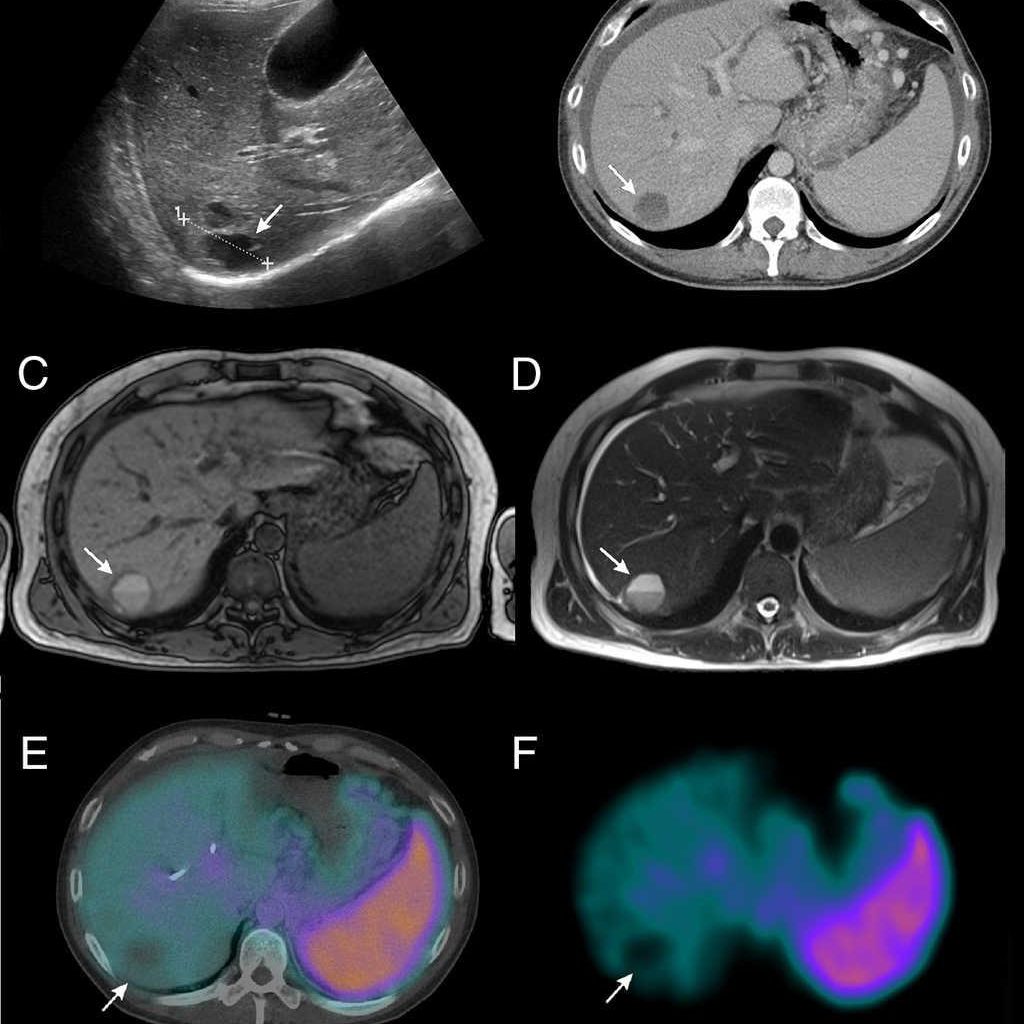

¿Cómo se realiza una gammagrafía ósea?

Una gammagrafía ósea implica inyectar una cantidad muy pequeña de material radiactivo (marcador) dentro de una vena. La sustancia viaja a través de la sangre hasta los huesos y órganos. A medida que esta va desapareciendo, emite un poco de radiación. Esta es detectada por una cámara que lentamente escanea el cuerpo.

Toma imágenes del marcador que hay en sus huesos. El técnico puede solicitarle que cambie de posición durante el procedimiento. Esto ayuda a obtener imágenes desde diferentes ángulos. Una gammagrafía ósea de todo el cuerpo tarda aproximadamente 1 hora en completarse.